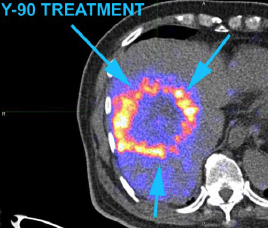

- 用正电子/电脑双融扫描显示钇90粒子分布(右)

99mTc MAA SPECT/CT Y-90 PET/CT

- 治疗後3个月正电子/电脑双融扫描

- 肝脏肿瘤代谢活跃度和体积减少

- 甲胎蛋白水平减少至1206 ng/ml

C-11 Acetate F-18FDG